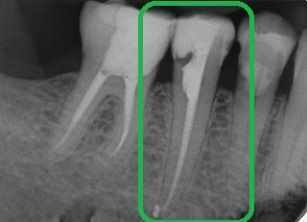

dente da devitalizzare

La cura canalare o devitalizzazione, in inglese root canal treatment, è la terapia che il dentista effettua sul dente colpito da un infezione penetrata fino alla polpa dentale. Solitamente la causa è una carie od una frattura che arrivano a danneggiare la barriera solida dello smalto permettendo l'ingresso dei batteri patogeni. La diagnosi di questa patologia viene eseguita effettuando in ambulatorio una lastra che permetterà al dentista di vedere chiaramente l'entità e la gravità dell'infezione. Questa infezione è chiamata pulpite (infezione della polpa dentale, per l'appunto) ed è estremamente dolorosa, poiché interessa la parte del dente che ospita i nervi sensoriali. Una volta che l'area della camera pulpare è invasa dai batteri, il dentista non può fare altro che asportare completamente la polpa, e di conseguena l'infezione, arrivando fino alle radici del dente. La cura canalare viene effettuata con il preciso scopo di preservare il dente dall'ulteriore estensione dell'infezione che, se trascurata, potrebbe giungere fino al tessuto parodontale ed all'osso, danneggiandoli gravemente. Questa degenerarzione sarebbe gravissima e l'unica terapia possibile in grado di curarla è l'innesto osseo. Pertanto, in presenza di dolore forte, è importante intervenire tempestivamente andando dal dentista per avere la diagnosi e le cure del caso. La cura canalare recupera l'elemento dentale che può continuare la sua vita funzionale dopo la terapia. La percentuale di successo è altissima, praticamente il 100% dei casi viene eseguito con successo.